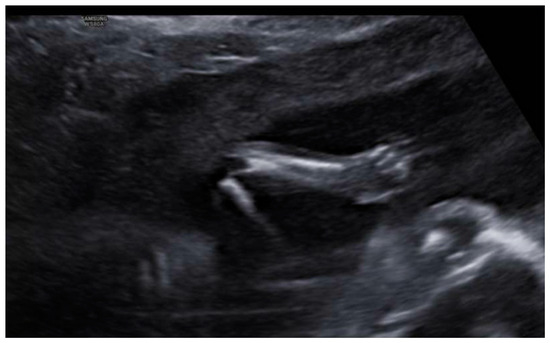

3. Results: Case Presentation

| Arthrogryposis | 80% | Yes | No |

| Syndactyly | 48% | No | No |